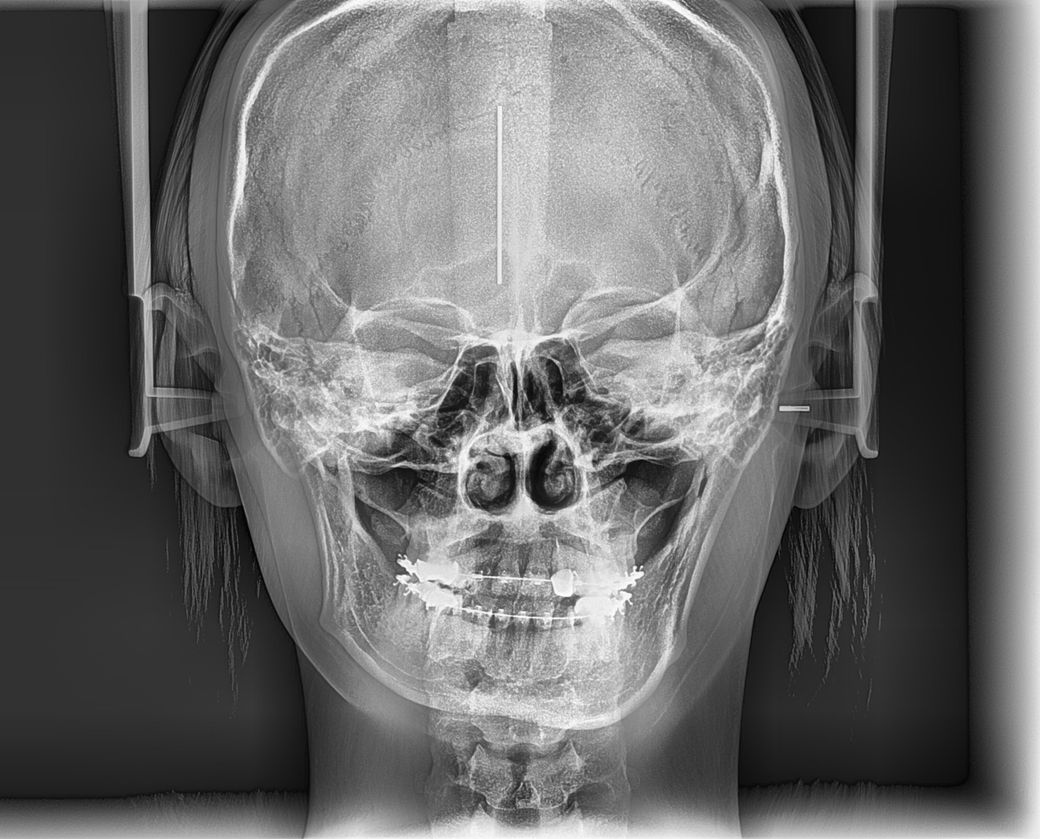

양악수술 부작용 어떠한 것들이 있을까요?

제가 부정교합이 있어서 원래는 양악수술 후에 교정을 해야 하나 최대한 교정으로 진행하는 중인લા 유의미한 결과는 나오지 않고, 벌써 3년넘게 교정 중입니다. 입을 벌릴 때 마다 딱딱 소리가 나요

제가 한쪽 턱뼈가 짧은લા 비대칭도 있어서 새로 양악을 하고 교정을 해야할지 고민 중입니다.. 양악 수술과 교정의 부작용이 어떤게 있을까요?

• 1번 째 사진

현재 교정 도중에 다시 양악을 고려하셨다면 교정을 다시하셔야 할 것으로 보입니다. 현재의 턱뼈 상황에서 교정이 되었기 때문에 양악 수술로 턱뼈를 교정하게 되면 현재의 치아 맞물림이 나타나지 않을 가능성이 크기 때문에 술전 교정을 다시 하셔야 할 것으로 보입니다. 보통 외과적 수술이기 때문에 나타날 수 있는 부작용은 모두 있고 턱뼈를 자르는 과정에서 신경이 손상되거나 과다 출혈이 나타날 수 있습니다. 하지만 과거에 비해 양악수술에 대한 안정성은 커졌고 대형 치과병원에서 한다면 큰 무리는 없어 보입니다. 정확한 판단을 위해 대학 병원 방문 후 검사 해보시길 추천드리며 다시 교정할 가능성이 커보입니다.